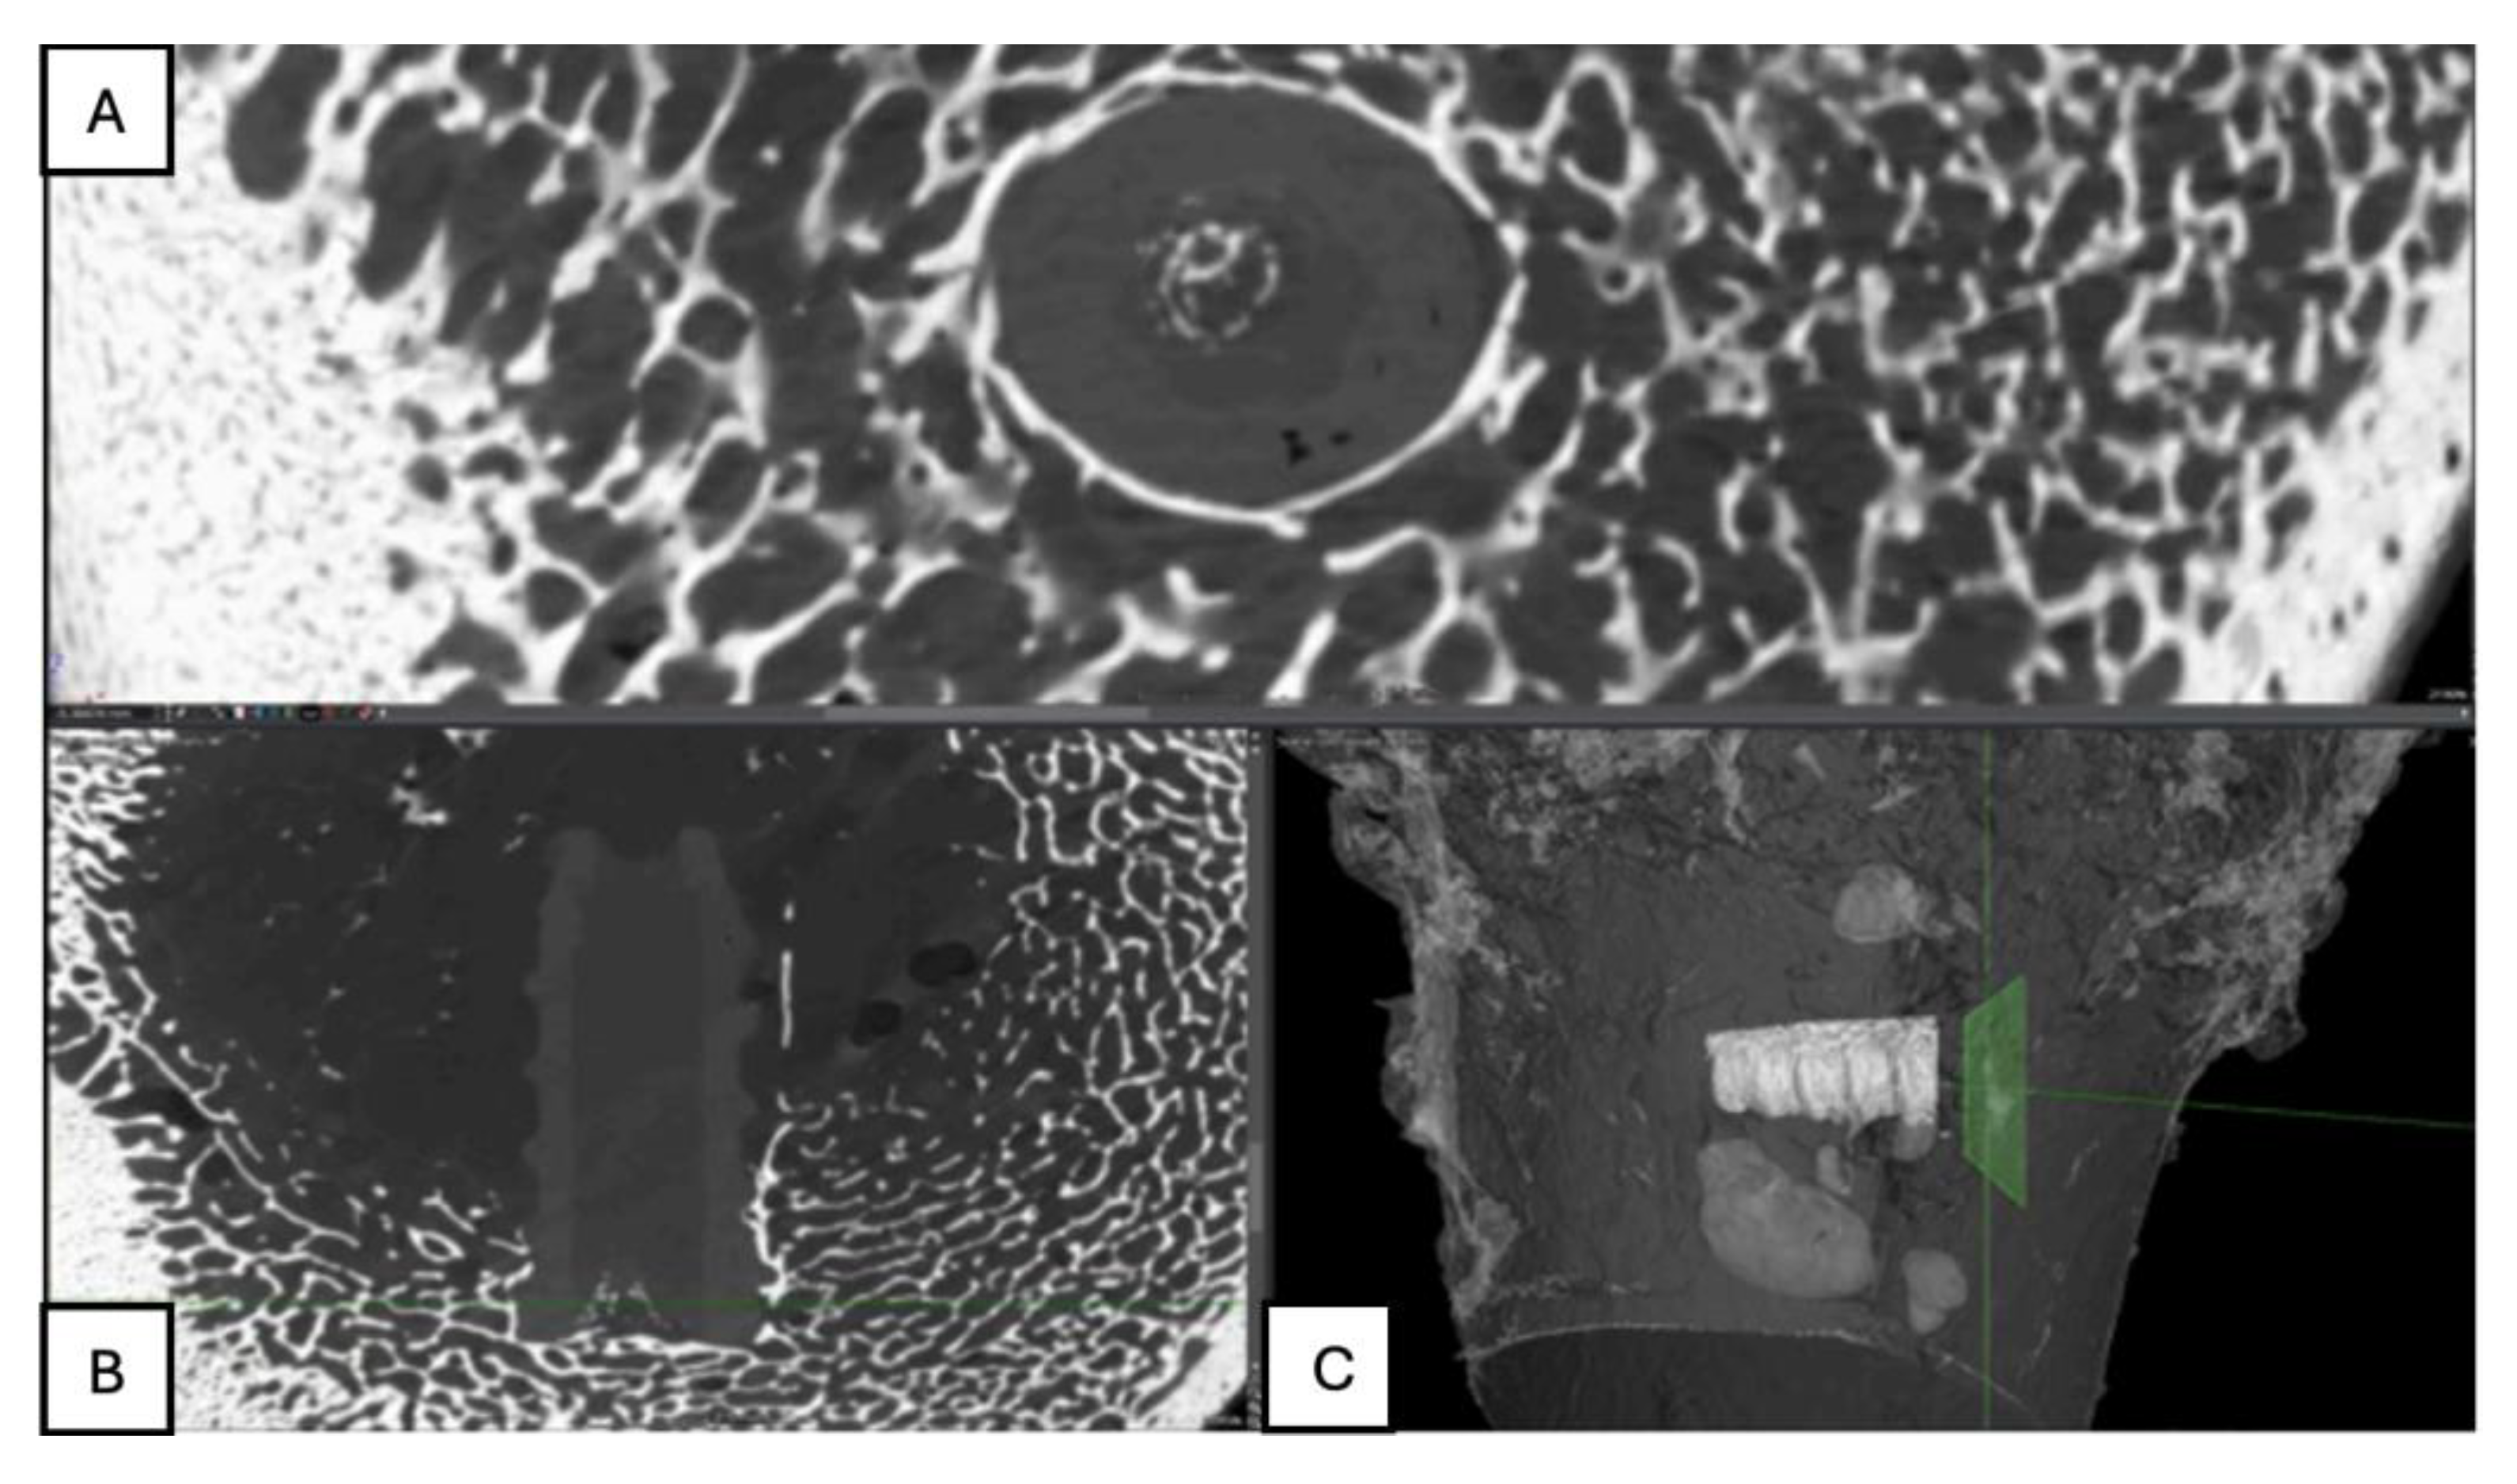

Figure 12. Computed tomography study of the right femur sample, one-month post-surgery, with PLA material. (A) axial slice, (B) sagittal reconstruction, and (C) 3D visualisation.

PLA: The right femur of the first surgically treated piglet at one-month post-operation was assessed through axial slices, sagittal reconstruction, and 3D visualisation. The PLA screw implant appeared perichondral positioned and perpendicular to the longitudinal axis of the bone (Figure 12).

PLA: The right femur of a surgically treated pig was examined after a three-month postoperative period using axial cuts, sagittal reconstruction, and 3D visualization. In the transverse section, a significant increase in bone trabeculation is observed, obstructing approximately 90% of the tunnel created for the insertion of the screw. In the sagittal view, an increase in circumferential hyperdensity around the screw is noted, indicating enhanced bone growth that contributes to a more stable fixation. (Figure 18)

PLA: Partial view of the left femur in a pig at a four-month postoperative follow-up, assessed through axial slices, sagittal reconstruction, and 3D visualization. Across all images, hyperdense areas identified, indicating bone growth into the interior of the PLA screw. Additionally, there is a partial increase in circumferential density toward the distal third of the screw, suggesting proper osseointegration and bone formation. (Figure 21)